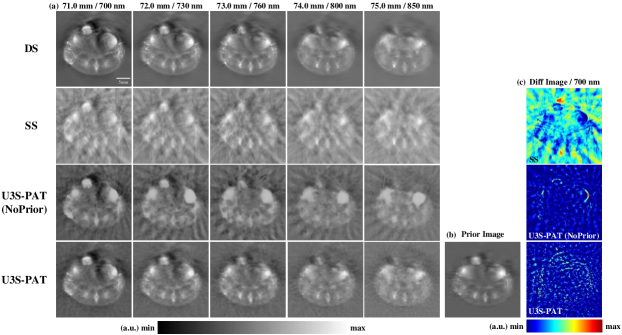

Fig.4 (a) and Fig.5 (a) display the image reconstruction results and the densely sampled (DS) reference images at different slice position and different wavelength. To investigate the impact of prior embedding, we also obtain the reconstruction results of U3S-PAT without the use of the prior image, i.e., random initialization is used during network training. As can be seen, both the sparsely sampled (SS) and U3S-PAT (NoPrior) methods suffer from significant background artifacts at the two transducer settings. In contrast, our U3S-PAT method effectively eliminates these artifacts, yielding reconstructed images of much better quality with well-defined anatomical structures and organ boundaries. When comparing Fig.4 (a) and Fig.5 (a), it could be seen that with even fewer transducer elements, the proposed method still produced acceptable results. In contrast, the image quality of the SS and U3S-PAT (NoPrior) reconstructions degraded heavily as the number of transducer elements decreased.

By comparing U3S-PAT with or without prior embedding, we observe that the introduction of prior significantly enhances image sharpness and reduces artifacts. Notably, despite utilizing the same prior image and relying solely on sparsely sampled data at each stage for image reconstruction, the resulting images accurately capture continuous tissue variations at different slice locations. To further observe the accuracy of the reconstructed images, absolute normalized error images between the reconstructed images obtained using each method and the corresponding reference images are calculated. Fig.4 (c) and Fig.5 (c) display the difference image between the reconstructed image at 21.0 mm / 700 nm and the corresponding DS reference. The U3S-PAT method exhibits the smallest error, emphasizing its superior performance compared to other methods. Moreover, comparing the results obtained from and , the U3S-PAT images vary little with the number of transducer elements, while the absolute difference images of SS and U3S-PAT (NoPrior) became significantly worse as fewer transducer are used.

Next, we perform quantitative evaluation of the image reconstruction results. We use peak signal noise ratio (PSNR) and structural similarity (SSIM) for evaluation, and the obtained results are presented in Table I. At , the U3S-PAT results showed an average increase of 120.48 in PSNR and 34.31 in SSIM compared to the SS results. At ND=16, the PSNR increased by 106.15 and SSIM increased by 39.25 on average. This means that the intensity values obtained by the U3S-PAT method are closer to the reference DS image in both settings. In addition, when and , U3S-PAT improves PSNR by 18.87 and 19.89, and SSIM by 16.70 and 18.30, respectively, compared to the U3S-PAT (NoPrior) method. U3S-PAT method consistently achieves superior performance across all metrics when utilizing prior embedding.